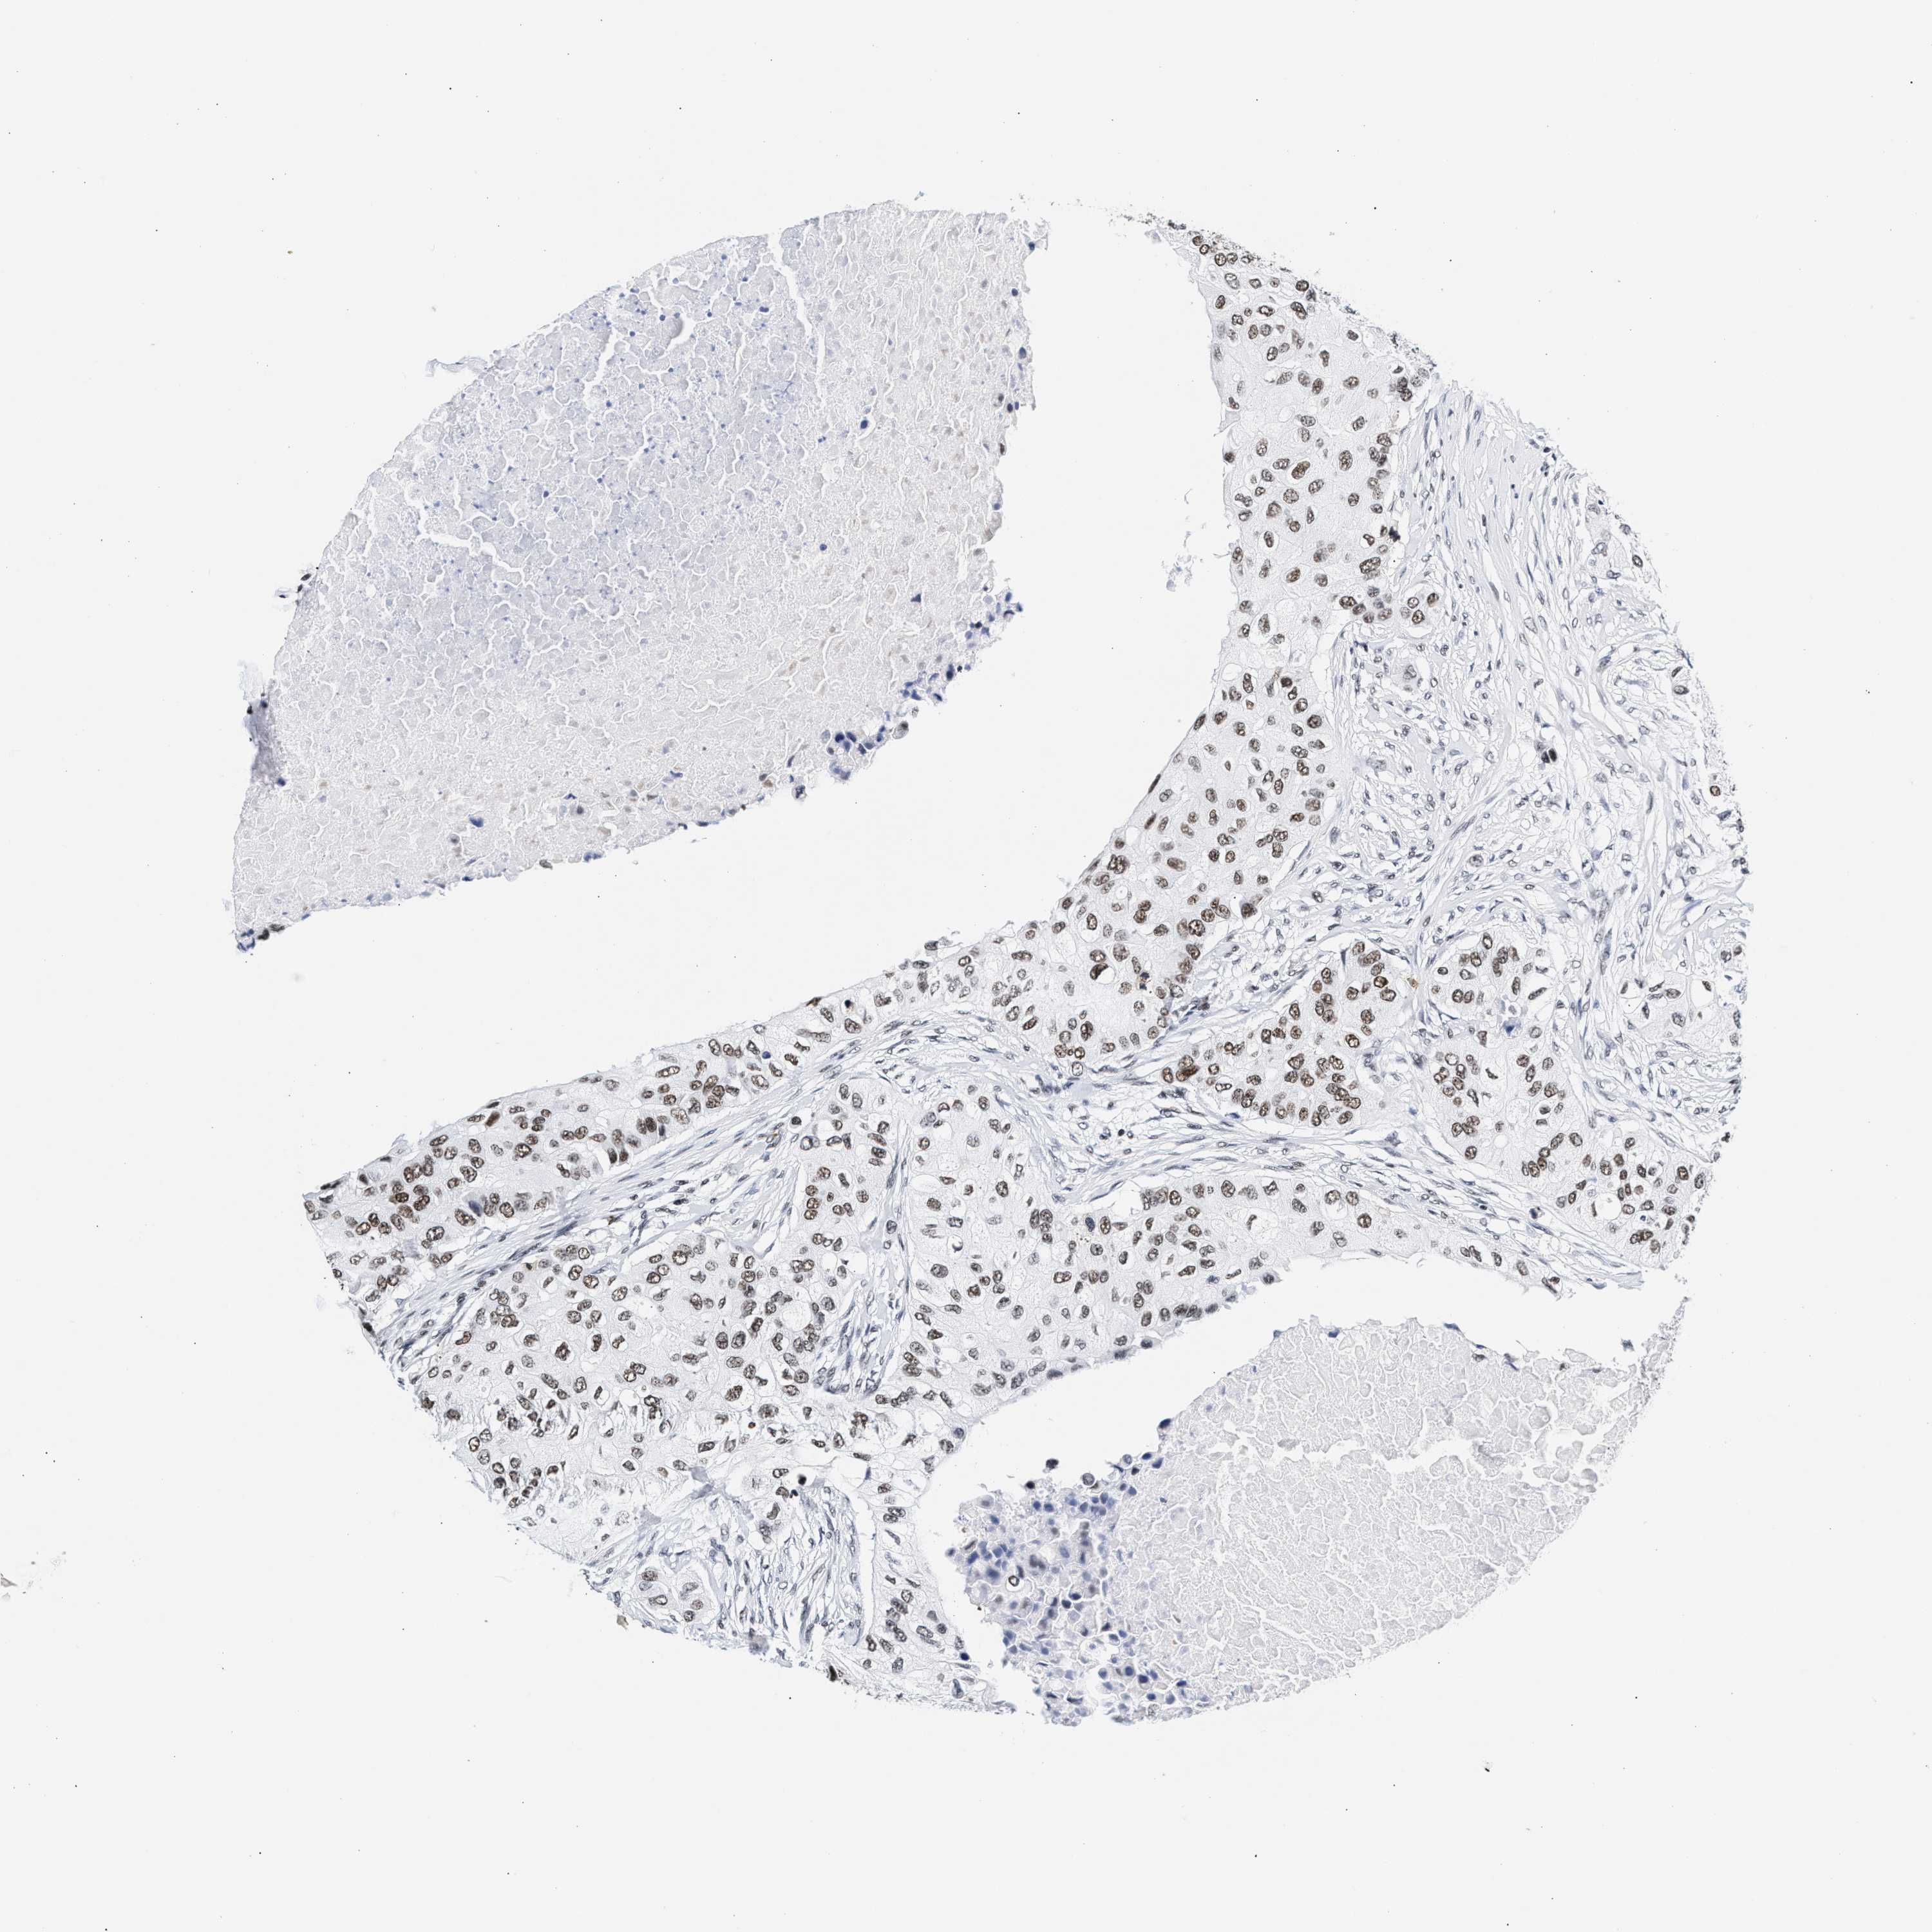

RAD21

CANCER BREAST CANCER Show tissue menu

BRCA TCGA BRCA VALIDATION PROTEIN EXPRESSION

ANTIBODIES

AND

VALIDATION